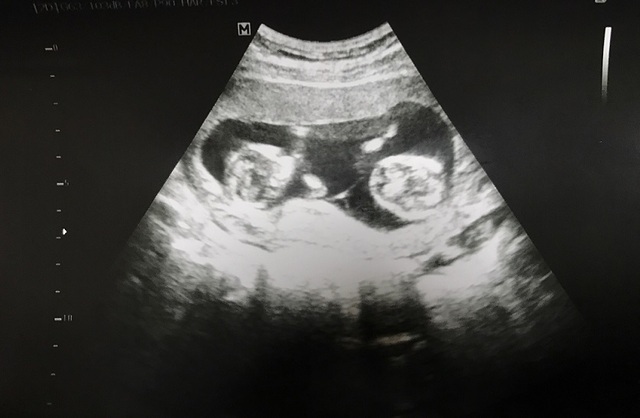

19週5日(19w5d・男の子)|グースケ さん(34歳)

エコー写真撮影時のエピソード:

里帰り出産にする予定で、実家の方の病院を受診した時に双子だと初めてわかりました。ビックリと同時に、二人とも元気で生まれてほしいと願っています。

双子は色々リスクがあるらしく、受診してエコーを撮るたびに二人が同じ様に成長してくれているかとても気になります。